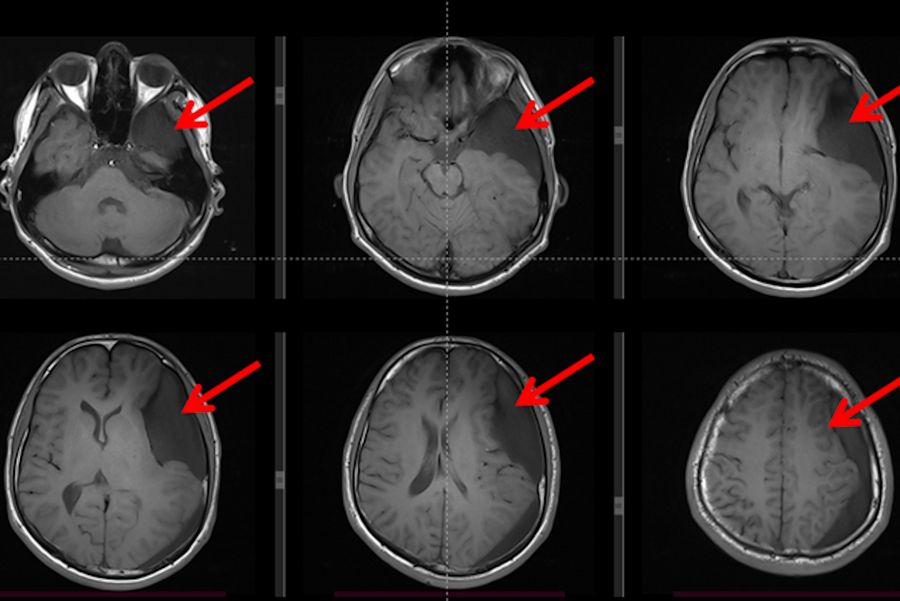

II. Pre-operative imaging assessment

The MRI exam results were used to plan the surgical procedure in detail and allowed to rule out any possible differential diagnosis beyond the arachnoid cyst. The T1WI weighted sequence of the brain MRI revealed a large arachnoid cyst (represented by red arrows) on the left side with a hypo-signal when compared to the brain, including a similar signal to cerebral spinal fluid, with no evidence of hemorrhage.

Fig. 2: T1 weighted brain MRI showing a large arachnoid cyst (represented by red arrows with a hypo-signal compared to the rest of the brain and iso-signal when compared to the  cerebrospinal fluid inside the ventricles).